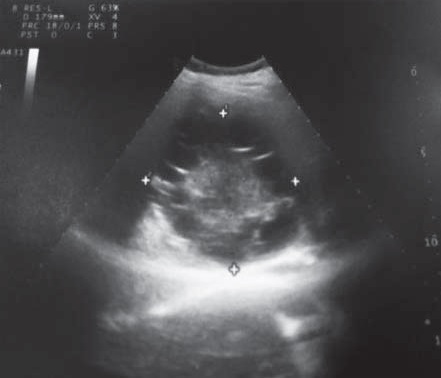

Для дальнейшего углубленного обследования и определения тактики лечения переведен в клинику военно-морской хирургии Военно-медицинской академии имени С.М. Кирова. В клинике выполнено комплексное клинико-лучевое обследование. При мультиспиральной компьютерной томографии (МСКТ) головы, грудной клетки, брюшной полости подтверждено наличие эхинококковой кисты правой доли печени около 10 см, которая сдавливает нижнюю полую вену (рис. 2, 3). В других органах и тканях эхинококк не выявлен. Пациент проконсультирован паразитологом – выставлен диагноз: эхинококковая киста печени.

Рис. 2. МСКТ эхинококковой кисты (многокамерная киста в правой доле диаметром 10 см)

Рис. 3. Компрессия нижней полой вены кистой